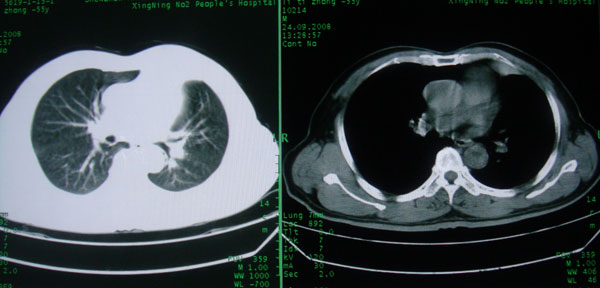

患者男性58岁因二周前起咳嗽,今天胸片示左上肺占位性病变行ct检查,无发热,无咯血痰.

左上肺感染性病变,结核伴空洞形成可能,左上肺膨胀不全

左肺上叶病灶,实变但见含气支气管、空洞但未见壁内结节及积液;

考虑:①感染性病变(包括特殊感染型肺tb)

②肿瘤性病变(考虑患者年龄比较大的关系/所以不排除)

初学者。。。左肺空洞性病变,并可见阻塞性肺不张改变,鉴于患者为老年男性,且临床症状仅有咳嗽,全身中毒症状不明显,所以我首先考虑为左肺癌性空洞并左侧肺门淋巴结转移伴左肺阻塞性肺不张。结核性空洞放于第二位考虑,可以进行相关实验室检查。希望能有病理结果,谢谢!!!!!

左肺上叶实变影,内见支气管充气征及空洞影,病人年龄较大,无发热及结核中毒症状,心影左移,未见纵隔淋巴结肿大;不知实验室检查结果如何?有否嗜酸细胞增多,有没有进行治疗?就目前资料首先考虑1.感染性病变,2.慢性嗜酸性肺炎?可结合实验室检查并短期治疗复查,肺癌不能排除。